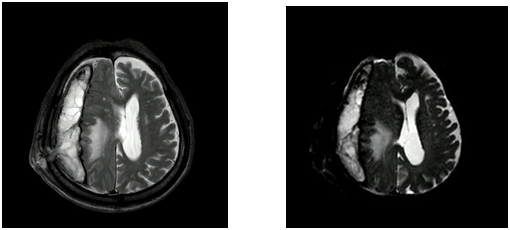

La resonancia magnética cerebral (véase Anexos) evidenció una restricción de difusión anormal en la difusión por resonancia magnética en el hemisferio derecho, altamente sugestivo de un absceso. El caso fue comentado con el grupo de infectología, que consideró necesario el uso de un antibiótico de alto espectro, por lo que se inició manejo con vancomicina y cefepima. El paciente fue llevado a cirugía de drenaje de la colección por medio de trepanación, con hallazgos intraquirúrgicos de una colección fétida subgaleal que se extendía a la piel y el espacio epidural, y una cavidad subdural con una cápsula fibrótica blanca gruesa sin presencia de material purulento en su interior. La resección quirúrgica fue completada sin complicaciones y se tomaron muestras para el análisis patológico. Los estudios histológicos mostraron áreas de necrosis, detritus celulares, fibrina e infiltración inflamatoria, principalmente de células polimorfonucleares. Se evidencio un área con presencia de bacterias grampositivas, cuyas características sugerían un diagnóstico de Actinomyces. Se realizaron tinciones de Ziehl-Neelsen, con ácido peryódico de Schiff (PAS) y plata, las cuales fueron negativas.